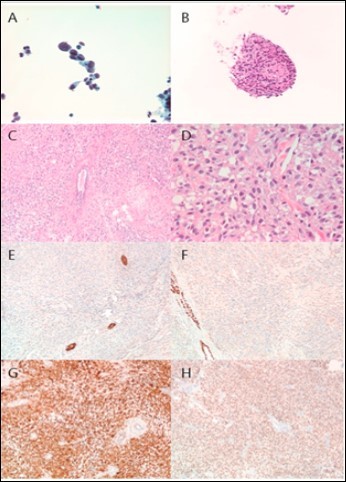

We report the case of a breast melanoma in a 75-year-old woman with a cancer history significant for ampullary adenocarcinoma for which she underwent surgery and chemoradiation approximately 9 years earlier. She presented to her oncologist with a left breast lump which appeared suddenly. There was no axillary lymphadenopathy. Diagnostic ultrasound and mammography revealed a 3.3 cm solid mass at 12 o’clock deep to the areola which approached the skin (Figure 1). Fine needle aspiration was performed at that time which was positive for malignant cells, consistent with a high grade sarcoma or spindle cell type carcinoma (Figure 2A,B). The malignant cells were focally positive for GATA3 and negative for ER and PR, and this was thought to represent a primary breast cancer. A metastasis from her ampullary adenocarcinoma was ruled out immunophenotypically. The patient chose to undergo mastectomy for definitive diagnosis and treatment.

Figure 2.Histopathological Findings. Fine needle aspiration revealed spindled, pleomorphic cells with numerous mitoses and apoptotic bodies. The cells were negative for cytokeratins and markers of breast, gastrointestinal, and hepatobiliary differentiation. Microscopic examination of the resected tumor revealed a poorly differentiated neoplasm with predominantly spindled morphology and diffuse expression of markers of melanocytic differentiation. A. Thinprep (40x), B. Cell block (H&E, 20x), C. H&E (10x), D. H&E (40x), E. Pan-cytokeratin (10x), F. GATA3 (10x), G. S100 (10x), H. SOX 10 (10x).

A mastectomy was performed without lymphadenectomy. Pathological examination revealed an irregularly shaped, homogenous tan/white mass which closely approached but did not involve the overlying skin. Immunohistochemical analysis revealed negativity for cytokeratins, EMA, myoepithelial markers, GATA3, mammaglobin, ER, and PR. The tumor cells were diffusely positive for S100, SOX10, and MITF1 and focally positive for HMB45, Melan-A, and MART-1. A diagnosis of malignant melanoma involving the breast was rendered (Figure 2C-H). The skin was entirely submitted, and no evidence of melanoma in situ or dermal lymphatic involvement was identified. Molecular characterization by next generation sequencing (NGS) revealed wild-type B-RAF, c-KIT, and N-RAS. However, the tumor was found to harbor a Smoothened oncogene (SMO) I408M substitution (gene locus 7q32.1), a mutation of uncertain significance in melanoma. A TP53 inframe deletion, a previously confirmed somatic mutation, was also identified. Sequencing of benign tissue from the same patient revealed no evidence of the SMO mutant, consistent with somatic origin.